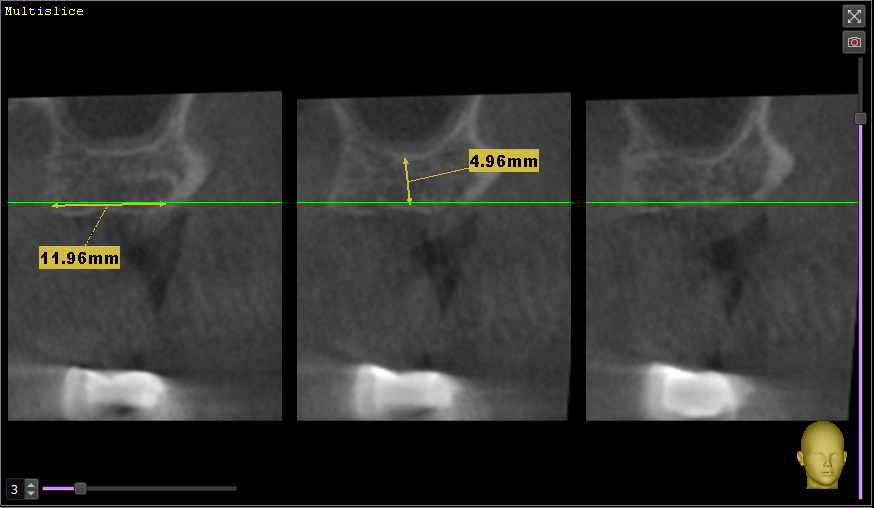

ЕвгенийПет Опубликовано 30 ноября, 2023 Поделиться Опубликовано 30 ноября, 2023 (изменено) Доброго дня! Уважаемые врачи, проблема и вопросы у меня в следующем: Примерно в 2010 году пришлось удалить 26 и 27 зубы (сначала свищ на одном, а со временем (около года) уже не помню почему и второй. С тех пор жую только на правую сторону, а сейчас под удаление 15 (снимок №1 во вложении), весной отекло лицо, обнаружили гранулему и вскрывали абсцесс. Тоже вопрос, хотя даже я по снимку вижу, что его не спасти, но а вдруг? Так вот, с жеванием теперь возникнут явные проблемы (отсутствует 46 зуб), и нужно срочно что-то решить со вторым рядом. Сразу скажу, что импланты сейчас не могу себе позволить, так как в прошлом году делал КТ, показывал хирургу, он сказал, что там перфорация и обязательно нужен синус-лифтинг (снимок №2 во вложении). Посмотрите, пожалуйста, это реально так? Без синус-лифтинга точно никак? Основной вопрос (снимок №3 вчера сделал) - врач предлагает сделать консольный мост с тремя коронками - с вкладкой на 24, закрыть 25 и созданный 26. Сразу скажу, что прошлым летом перелечивал канал в 24 и ставил на него металлокерамику на двух штифтах (один уже был ранее, второй добавили), но она сломалась месяц назад, чуть более года (из-за этого у меня вообще недоверие к коронкам, у меня 35 зуб только корень, на нем сделана пломба, и он стоит уже 7 лет без проблем). Первый основной вопрос - хорошо ли пролечены каналы в 24 и 25 зубах под мост? И второй основной вопрос - насколько будет прочна конструкция консольного моста, с учетом отсутствия 27? какие риски продолжения разъезжания ряда (за эти 14 лет эта сторона и так уже прилично разъехалась)? Момент еще в том, что сильно выросли за это время 36 и 37 зубы, там буквально милиметр остается для новых 26 и 27 зубов. Ранее другой врач мне советовал сделать мост с опорами на 28 и 24+25, но текущий врач такое даже не рассматривает, говорит, что 28 кривой уже (не депульпирован) и такая конструкция сломается быстро, а консольный 24+25+26 будет надежнее. Прошу помощи и консультации, что можно сделать в данной ситуации кроме имплантов. Заранее благодарю! И менее важный вопрос - позавчера депульпировал 36 зуб, посмотрите, пожалуйста (снимок №4), хорошо ли пролечены каналы? Спасибо! Изменено 30 ноября, 2023 пользователем ЕвгенийПет Ссылка на комментарий

wladdX Опубликовано 6 декабря, 2023 Поделиться Опубликовано 6 декабря, 2023 Измерения в зоне 26 и 27 2 Ссылка на комментарий